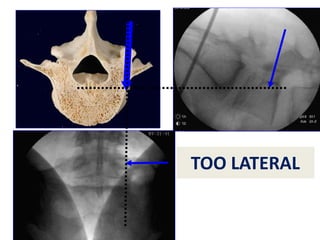

ENTRY POINT

MID-PEDICLE

NC JUNCTION

TOO MEDIAL

TOO LATERAL